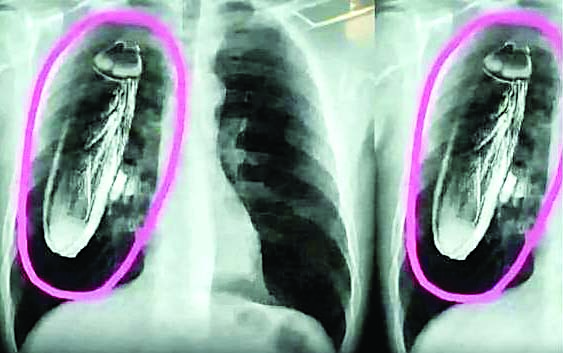

विभागीय अधिकारियों ने लोगों से इस तरह की वायरल पोस्ट से परहेज करने की भी सलाह दी है। सोलन, शिमला और बद्दी के अस्पताल की कहानी लिख वायरल हो रही एक्स-रे कॉपी से लोग परेशान हो गए हैं। इसका प्रभाव अस्पताल में होने वाले एक्स-रे में भी पड़ा है। शुक्रवार देर रात से एक्स-रे कॉपी वायरल हो रही है। क्षेत्रीय अस्पताल में रोजाना से कम एक्स-रे हुए हैं। पोस्ट के वायरल होते ही स्वास्थ्य मंत्री ने भी क्षेत्रीय अस्पाल सोलन प्रबंधन से भी बात की और इसकी सत्यता जानी। सोशल मीडिया में वायरल हुए पोस्ट में तीन एक्स-रे कॉपी लगी है।

साथ ही पोस्ट किया है कि क्षेत्रीय अस्पताल सोलन में एक सिंगापुर से आए पर्यटक को सीने में दर्द हुई। इसके बाद वे उपचार के लिए सरकारी अस्पताल आए और वहां एक्स-रे करवाया। एक्स-रे की रिपोर्ट में उन्हें बताया कि सीने में जिंदा कॉकरोच है।

इसके बाद उन्हें तुरंत सिंगापुर जाने के लिए भी कहा। मरीज वापस सिंगापुर भी लौट गया और चिकित्सक की ओर से जांच के दौरान पाया कि कॉकरोच मरीज की छाती में नहीं बल्कि एक्स-रे मशीन में था। शिमला में इसे एडिट कर शिमला , बद्दी में भी क्षेत्रीय अस्पताल सोलन की जगह बद्दी किया है, लेकिन वास्तव में ऐसा कुछ भी नहीं हुआ है। क्षेत्रीय अस्पताल सोलन के चिकित्सा अधीक्षक डा. राकेश पंवार ने बताया कि सोशल मीडिया में पोस्ट देखी है। यह एक भ्रामक पोस्ट है और एआई से बनाई गई है।